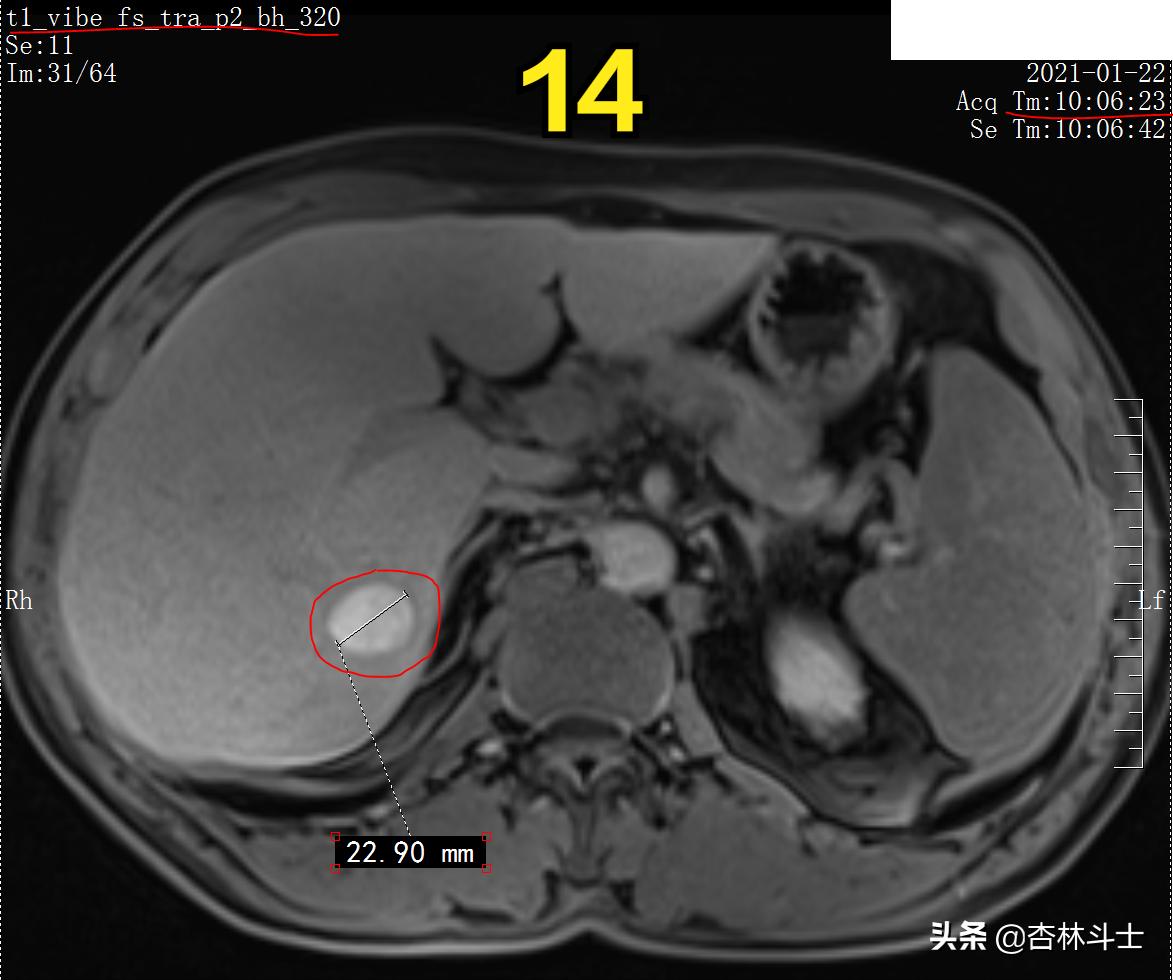

图14 T1加权压脂 肝胆特异期

图12-16 持续20余分钟,病灶内仍有特异性对比剂。

总结:病灶呈类圆形,直径约22㎜(体积约5575立方毫米)( 5角硬币:直径为20.5mm )T1上呈不均匀高信号内部可见等信号,T1同反相位,病灶信号无明显变化,T1压脂病灶信号略减低;T2呈不均匀高信号;动脉期明显不均匀强化;门静脉期强化未见减退且与周围肝实质相比仍呈高信号;平衡期及肝胆特异期,病灶仍呈高信号。

根据患者影像学特点并结合患者临床资料,当时影像科大夫给的影像诊断是 肝血管平滑肌脂肪瘤, 其他疾病不排除,建议定期随诊。